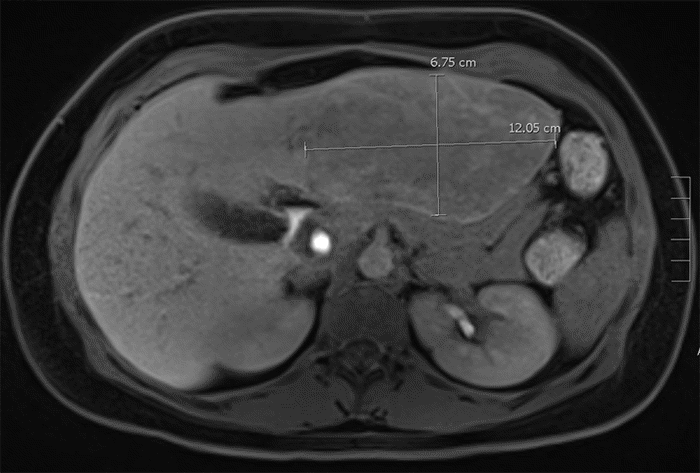

Figure 1. Preoperative Liver MRI. Published with Permission

(A) Axial coronal gadoxetate-enhanced MRI liver image demonstrating a 10.6 × 12.1 × 6.8 cm left lobe segment II-IV lesion exhibiting heterogeneous enhancement that persists into the hepatobiliary phase, along with a T2-hypointense central scar. Additionally, two areas consistent with focal nodular hyperplasia are identified in segments IVb and VI, along with three small (~1 cm) lesions likely consistent with hepatic adenomas in segments VI and VII

(B) coronal gadoxetate-enhanced MRI liver image demonstrating a 10.6 × 12.1 × 6.8 cm left lobe segment II-IV lesion exhibiting heterogeneous enhancement that persists into the hepatobiliary phase, along with a T2-hypointense central scar. Additionally, two areas consistent with focal nodular hyperplasia are identified in segments IVb and VI, along with three small (~1 cm) lesions likely consistent with hepatic adenomas in segments VI and VII.